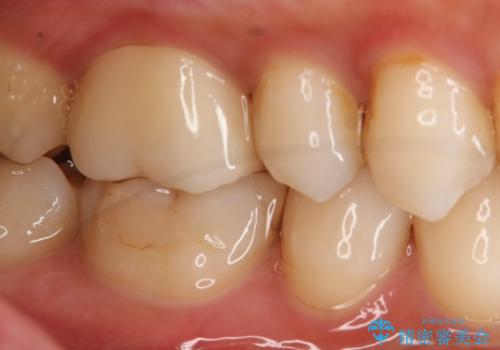

- 右上下6番の銀歯のやり変えを希望された患者様です。

切削量・形態を考慮し、上はセラミッククラウン、下はセラミックインレーでの治療を選択しました。

上はう蝕が歯頚部まで達していたのでクラウンでの治療を選択しました。

下はクラウンほど切削量が多くないと判断し、インレーでの治療を選択しました。